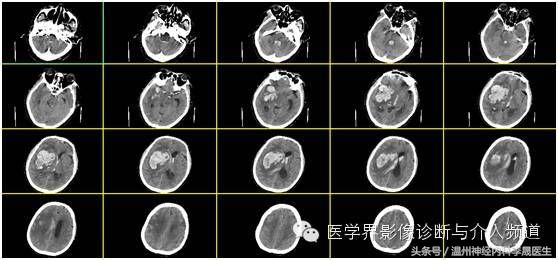

血肿量计算法。血肿量=长×宽×层面×π/6

脑出血CT全图

最大层面测量图

选取血肿最大层面,测量长宽径线,如果在胶片中,可以比对下方的刻度,一小格为1 cm。

出血量≈4.90×5.74×5.0÷2≈70 ml,但未包括破入脑室的出血量。